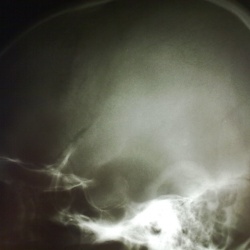

Женщина, 40 лет. Упала в обморок - решила обследоваться. Нашел вот такую "штуковину"